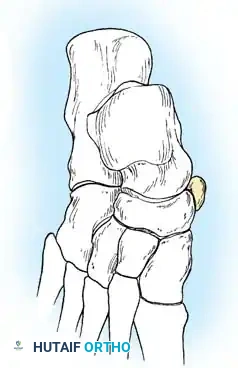

Radiographic Imaging

The 45-degree lateral oblique radiograph is the gold standard for diagnosing a calcaneonavicular coalition. The abnormal bar extends from the anterior process of the calcaneus (just lateral to the anterior facet) dorsally and medially to the lateral/dorsolateral extra-articular surface of the navicular. It typically measures 1 to 2 cm in length and 1 to 1.2 cm in width.

In incomplete coalitions, the adjacent bony margins appear irregular, sclerotic, and indistinct. The talar head may also appear small and underdeveloped.

While standard anteroposterior and lateral radiographs may show secondary signs (such as the "anteater nose" sign for calcaneonavicular coalitions or the "C-sign" and talar beaking for talocalcaneal coalitions), advanced imaging is often utilized in modern practice.

Advanced Imaging and Anatomical Reference Gallery

The following images illustrate various presentations, surgical exposures, and advanced imaging modalities (including CT and MRI correlates) utilized in the comprehensive evaluation and treatment of rigid pes planus and tarsal coalitions: